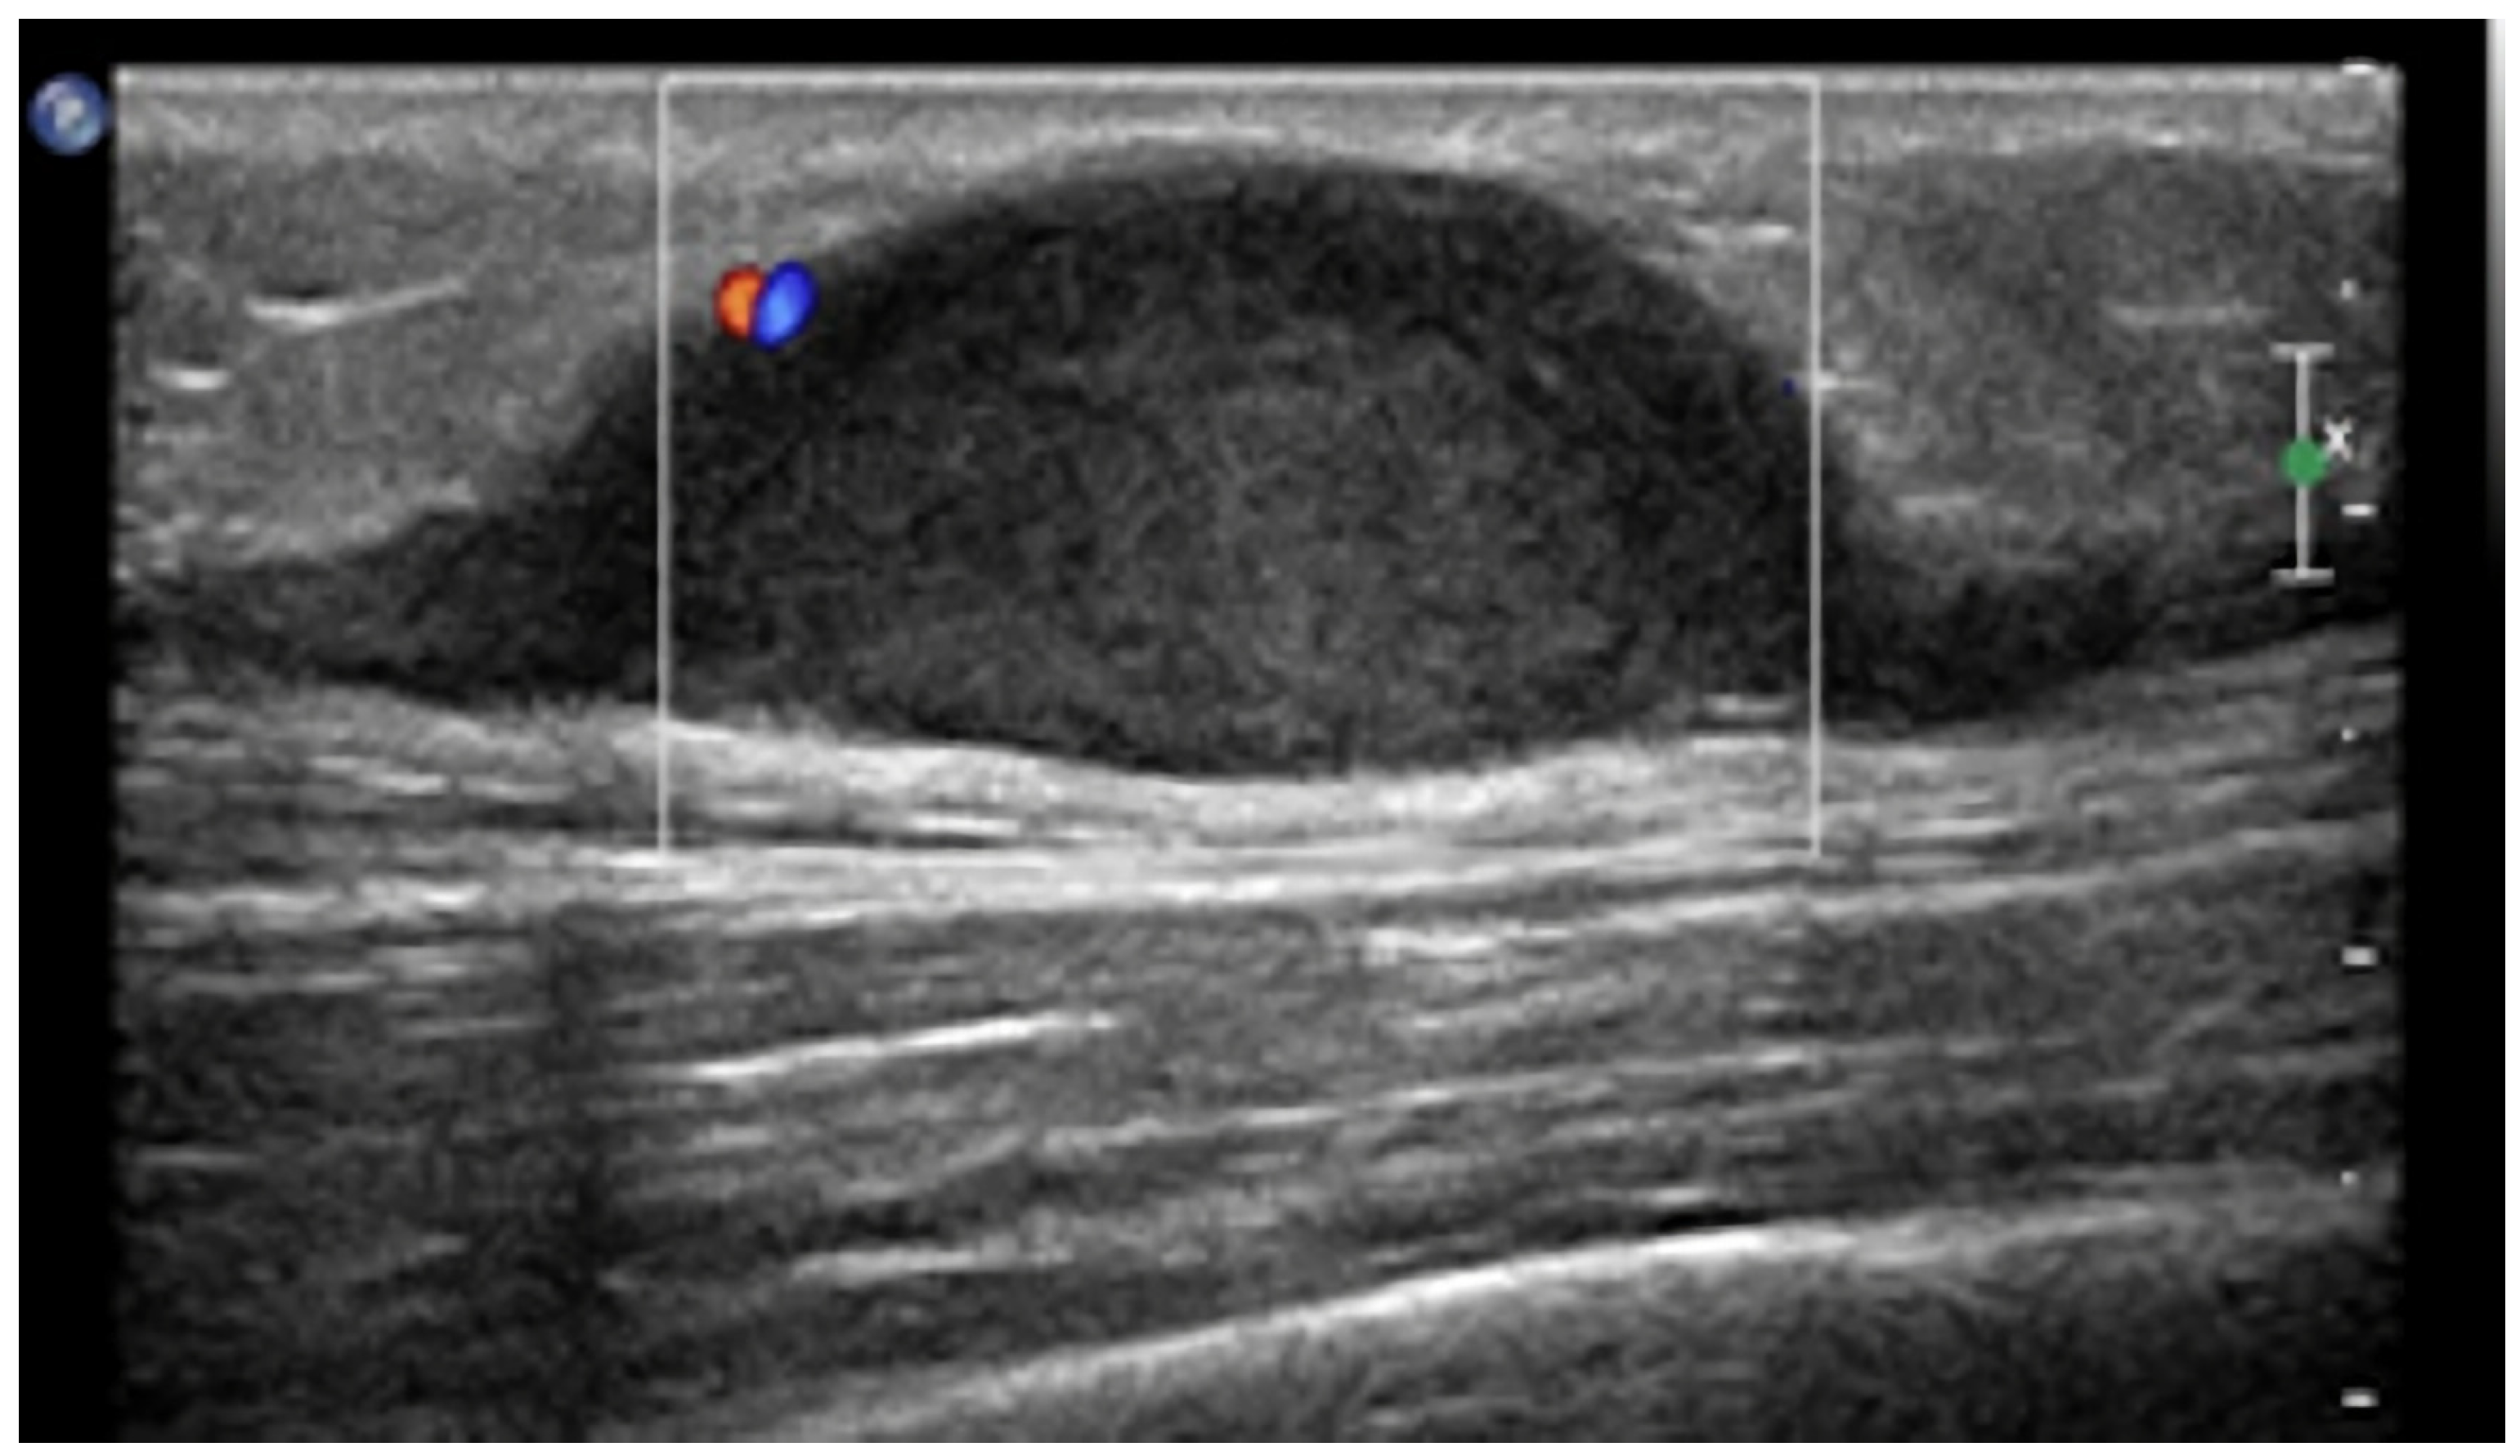

2.3. Hemangioma

| Hemangioma |

|